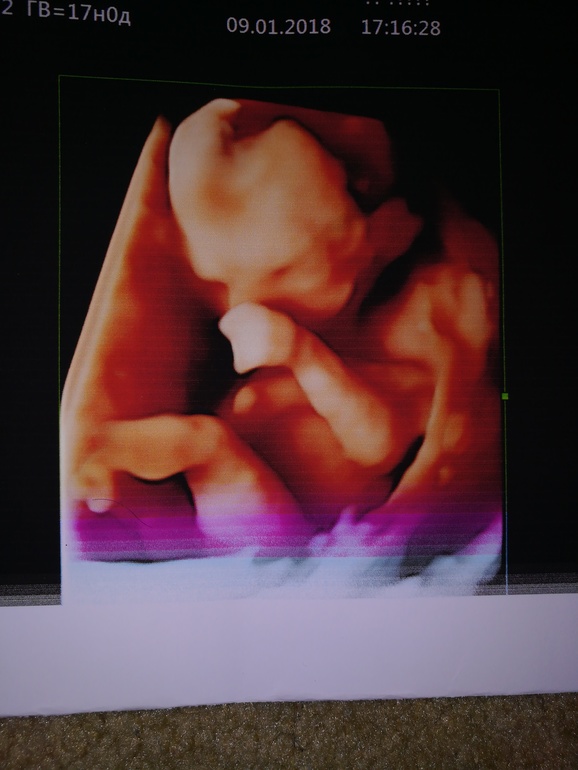

У нас в 12 недель вообще ничего понятно не было, от тонуса сплющило ребенка. Фото есть 3д, какой-то червячок😁 в 17 недель поинтереснее было. Сейчас в ютубе посмотрела узи в 24 недели 3д, здорово так личико показывает малыш🤗🤗 ушки, носик, ротик видно, как губами шевелит, ручки к лицу подносит. Но наш любитель прятать лицо, не знай покажет нет папе.

вот такое вот узи в 12 недель было у нас. Тонус, чтоб его

вот в 17